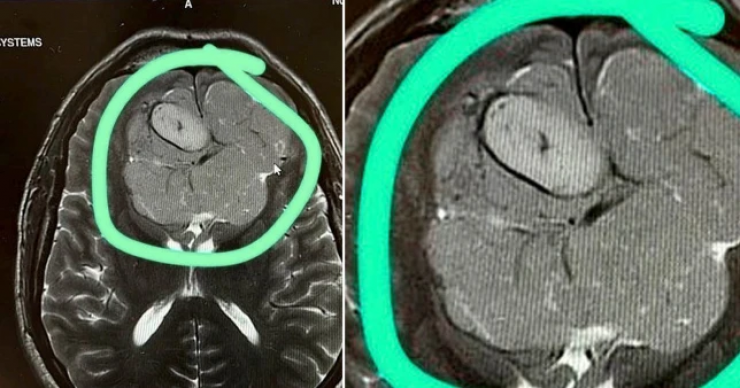

На следующий день специалисты с помощью МРТ выяснили, что зрение у мужчины упало из-за большой опухоли. Новообразование давило на мозг.

Фото:Jonathan Jones/SWNS